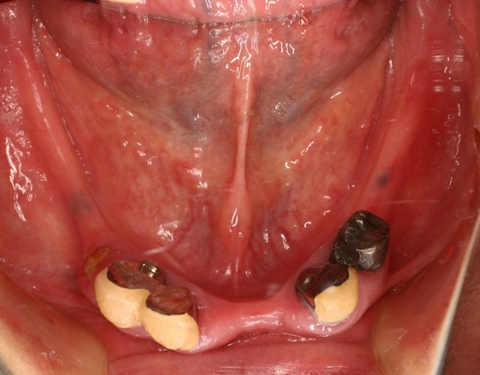

両側5歯症例

両側5歯症例両側5歯症例両側5歯症例 主訴-義歯のバネが壊れて手前の歯が痛んできた。 術前(旧義歯装着、鏡像) 術前(下顎粘膜面、鏡像)術前(下顎粘膜面、鏡像)術前(下顎粘膜面、鏡像) 術前レントゲン術前レントゲン術前レントゲン 術前口腔内(正面観)術前口腔内(正面観)術前口腔内(正面観)

術後(鏡像)術後(鏡像)術後(鏡像) 術後口腔内(正面観)術後口腔内(正面観)術後口腔内(正面観)もう入れ歯は要らなくなりました。 術後レントゲン術後レントゲン術後レントゲン